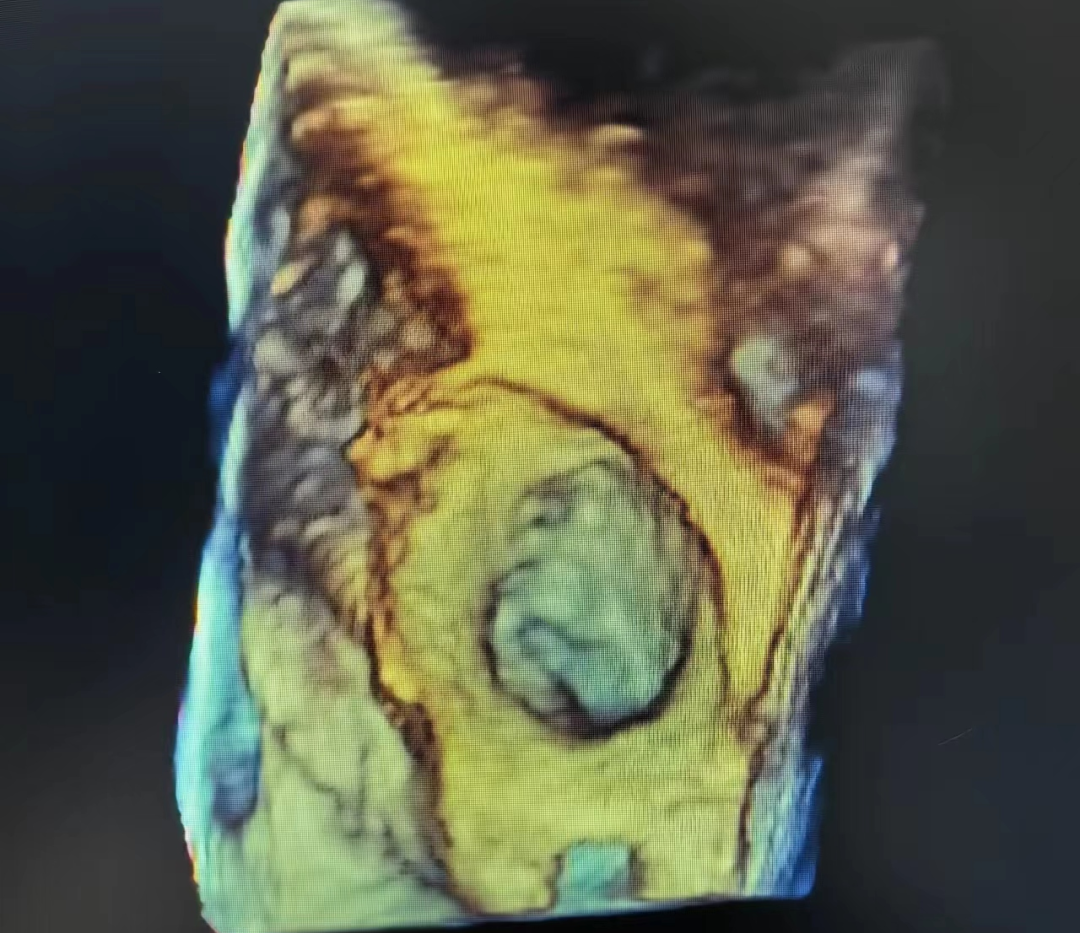

经食管超声心动图检查(TEE)是将食道超声探头置于食管或胃底,从心脏后方探查心脏及大血管解剖结构和血流信息的影像诊断技术。近年来,经食管超声心动图检查已经在临床得到广泛应用,对心血管疾病的诊断、治疗以及疗效评价产生了巨大影响,逐渐成为心血管疾病的主要诊疗方法和金标准。

您好!与普通的胸部超声相比,TEE探头直接贴近心脏后方扫查,明显缩短了探头与心脏及其周围大血管的距离,同时也不受肋骨、胸骨、肺及皮下脂肪的干扰,因此图像更清晰,尤其对于心脏后部结构,如对房间隔、主动脉瓣、二尖瓣、左心耳及胸主动脉等结构的显示更具有优势。